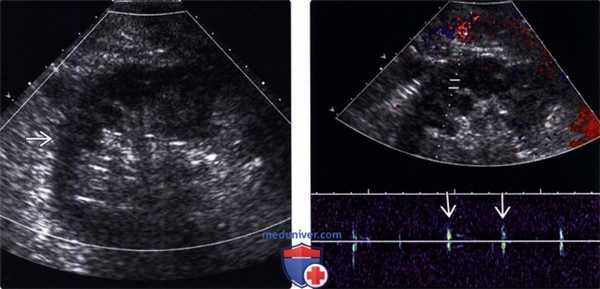

(Левый) На продольном УЗ срезе с цветовой допплерографией в первые сутки после трансплантации почки не визуализируется цветовой поток в трансплантате вследствие раннего тромбоза у пациента с гиперкоагуляцией.

(Правый) На продольном УЗ срезе с импульсно-волновой допплерографией у этого же пациента отсутствует артериальный поток в трансплантате. Шумы проводились к почке.